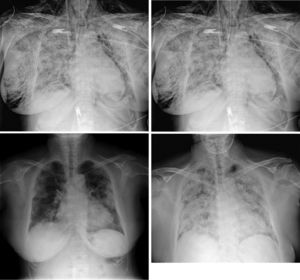

Two hours later, he presented blood oxygen desaturation with significant subcutaneous emphysema, mainly in the cervical spine and right hemithorax, with crepitus during palpation (Fig. 2), that could have been secondary to traumatic orotracheal intubation associated with bag mask ventilation during his transfer to the ICU. The patient presented multiple organ failure, and died.

Anteroposterior chest X-ray, in decubitus. Extensive subcutaneous emphysema that extends through the supraclavicular fossae, shoulders, dissects the left pectoral muscle and the right breast. Note the presence of air in the left paratracheal line at the mediastinal level, which surrounds the aortic knob and to a lesser extent the left cardiac margin - findings compatible with pneumomediastinum, with no associated pneumothorax.